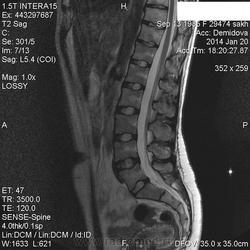

Вторая пациентка:

В телах позвонков определяются множественные очаги и фокусы разной степени интенсивности понижения МР-сигнала по Т1, Т2 ( первые 2 картинки), неоднородного повышения по Т2 с жироподавлением ( третьи картинки).

Контрастирование  не проводили.